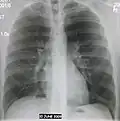

- Normal AP CXR

-

Normal lateral CXR -

AP CXR showing left lower lobe pneumonia associated with a small left sided pleural effusion -

AP CXR showing right lower lobe pneumonia -

AP CXR showing pneumonia of the lingula of the left lung -

Right upper lobe pneumonia as marked by the circle. - Left upper lobe pneumonia with a small pleural effusion.

- Right lower lobe pneumonia as seen on a lateral CXR